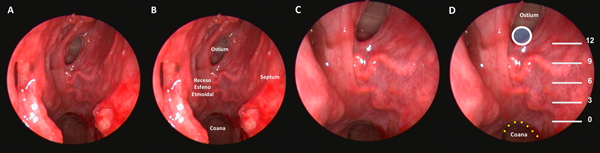

El próximo paso es identificar el ostium esfenoidal del lado derecho. Si el mismo no es visible, la maniobra más recomendada para identificarlo es utilizar un disector de Cottle para lateralizar el cornete superior en la unión de su tercio medio y posterior. Si aun así no logra identificarse, se procede palpando sin presionar demasiado en esta región hasta identificar una zona débil fenestrando delicadamente la mucosa. Se realiza finalmente un movimiento rotacional con el disector para ampliarlo (Figura 2 A-B).

La zona más baja del ostium coindice con el “punto de Cappabianca”, 12 mm por arriba del techo de la coana.10 (Figura 3 A-D) A partir de este punto comenzamos el tallado de un “mini-rescue flap” septal del lado derecho. Utilizamos una punta de colorado de 45 grados a tales efectos. Se trata de una modificación del rescue flap que utiliza el equipo de Ohio11; el corte anterior se efectúa buscando la proyección de la unión osteo-cartilaginosa septal (Figura 2 C-E).

Figura 3. Preparado cadavérico que muestra reparos a la hora de tallar el mini-rescue flap. A: receso esfeno-etmoidal. B: ídem a A con nomenclatura. C: zoom para evidenciar arteria esfenopalatina en receso esfeno-etmoidal. D: correlación entre el punto de Cappabianca (circulo celeste con borde blanco) y el borde inferior del ostium esfenoidal.

Figura 4. Tiempo intrasinusal. A-D: exposición de la duramadre selar.